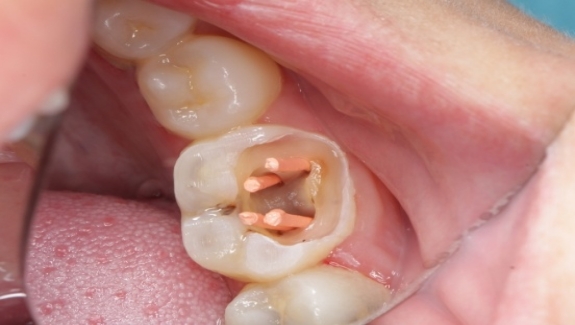

根管治疗的原则是什么 根管治疗是通过根管预备,彻底清理髓腔,消除感染源,经根管消毒将残存在髓腔内及牙本质小管内的细菌及其毒素进行消毒,并用根管充填剂严密填塞死腔,防止再感染,从而预防... 根管治疗 丘乐正 695 2024-01-16

根管治疗的原则有哪些 根管治疗首创于18世纪英国J.Hunter,初期只是限于拔髓和单独的药物消毒,随着细菌学和根管微结构研究的发展,促进了根管预备(机械预备和化学预备)、根管消毒和... 根管治疗 仙千风 967 2023-12-15

根管治疗为什么那么贵 牙齿出现了疼痛,很多情况医生都会建议患者进行根管治疗也就是老百姓常说的抽神经,其实很多人并不懂牙齿有洞出现了疼痛为什么不能直接补一下,而是非要选择抽神经。... 根管治疗 笪冰夏 575 2023-11-08